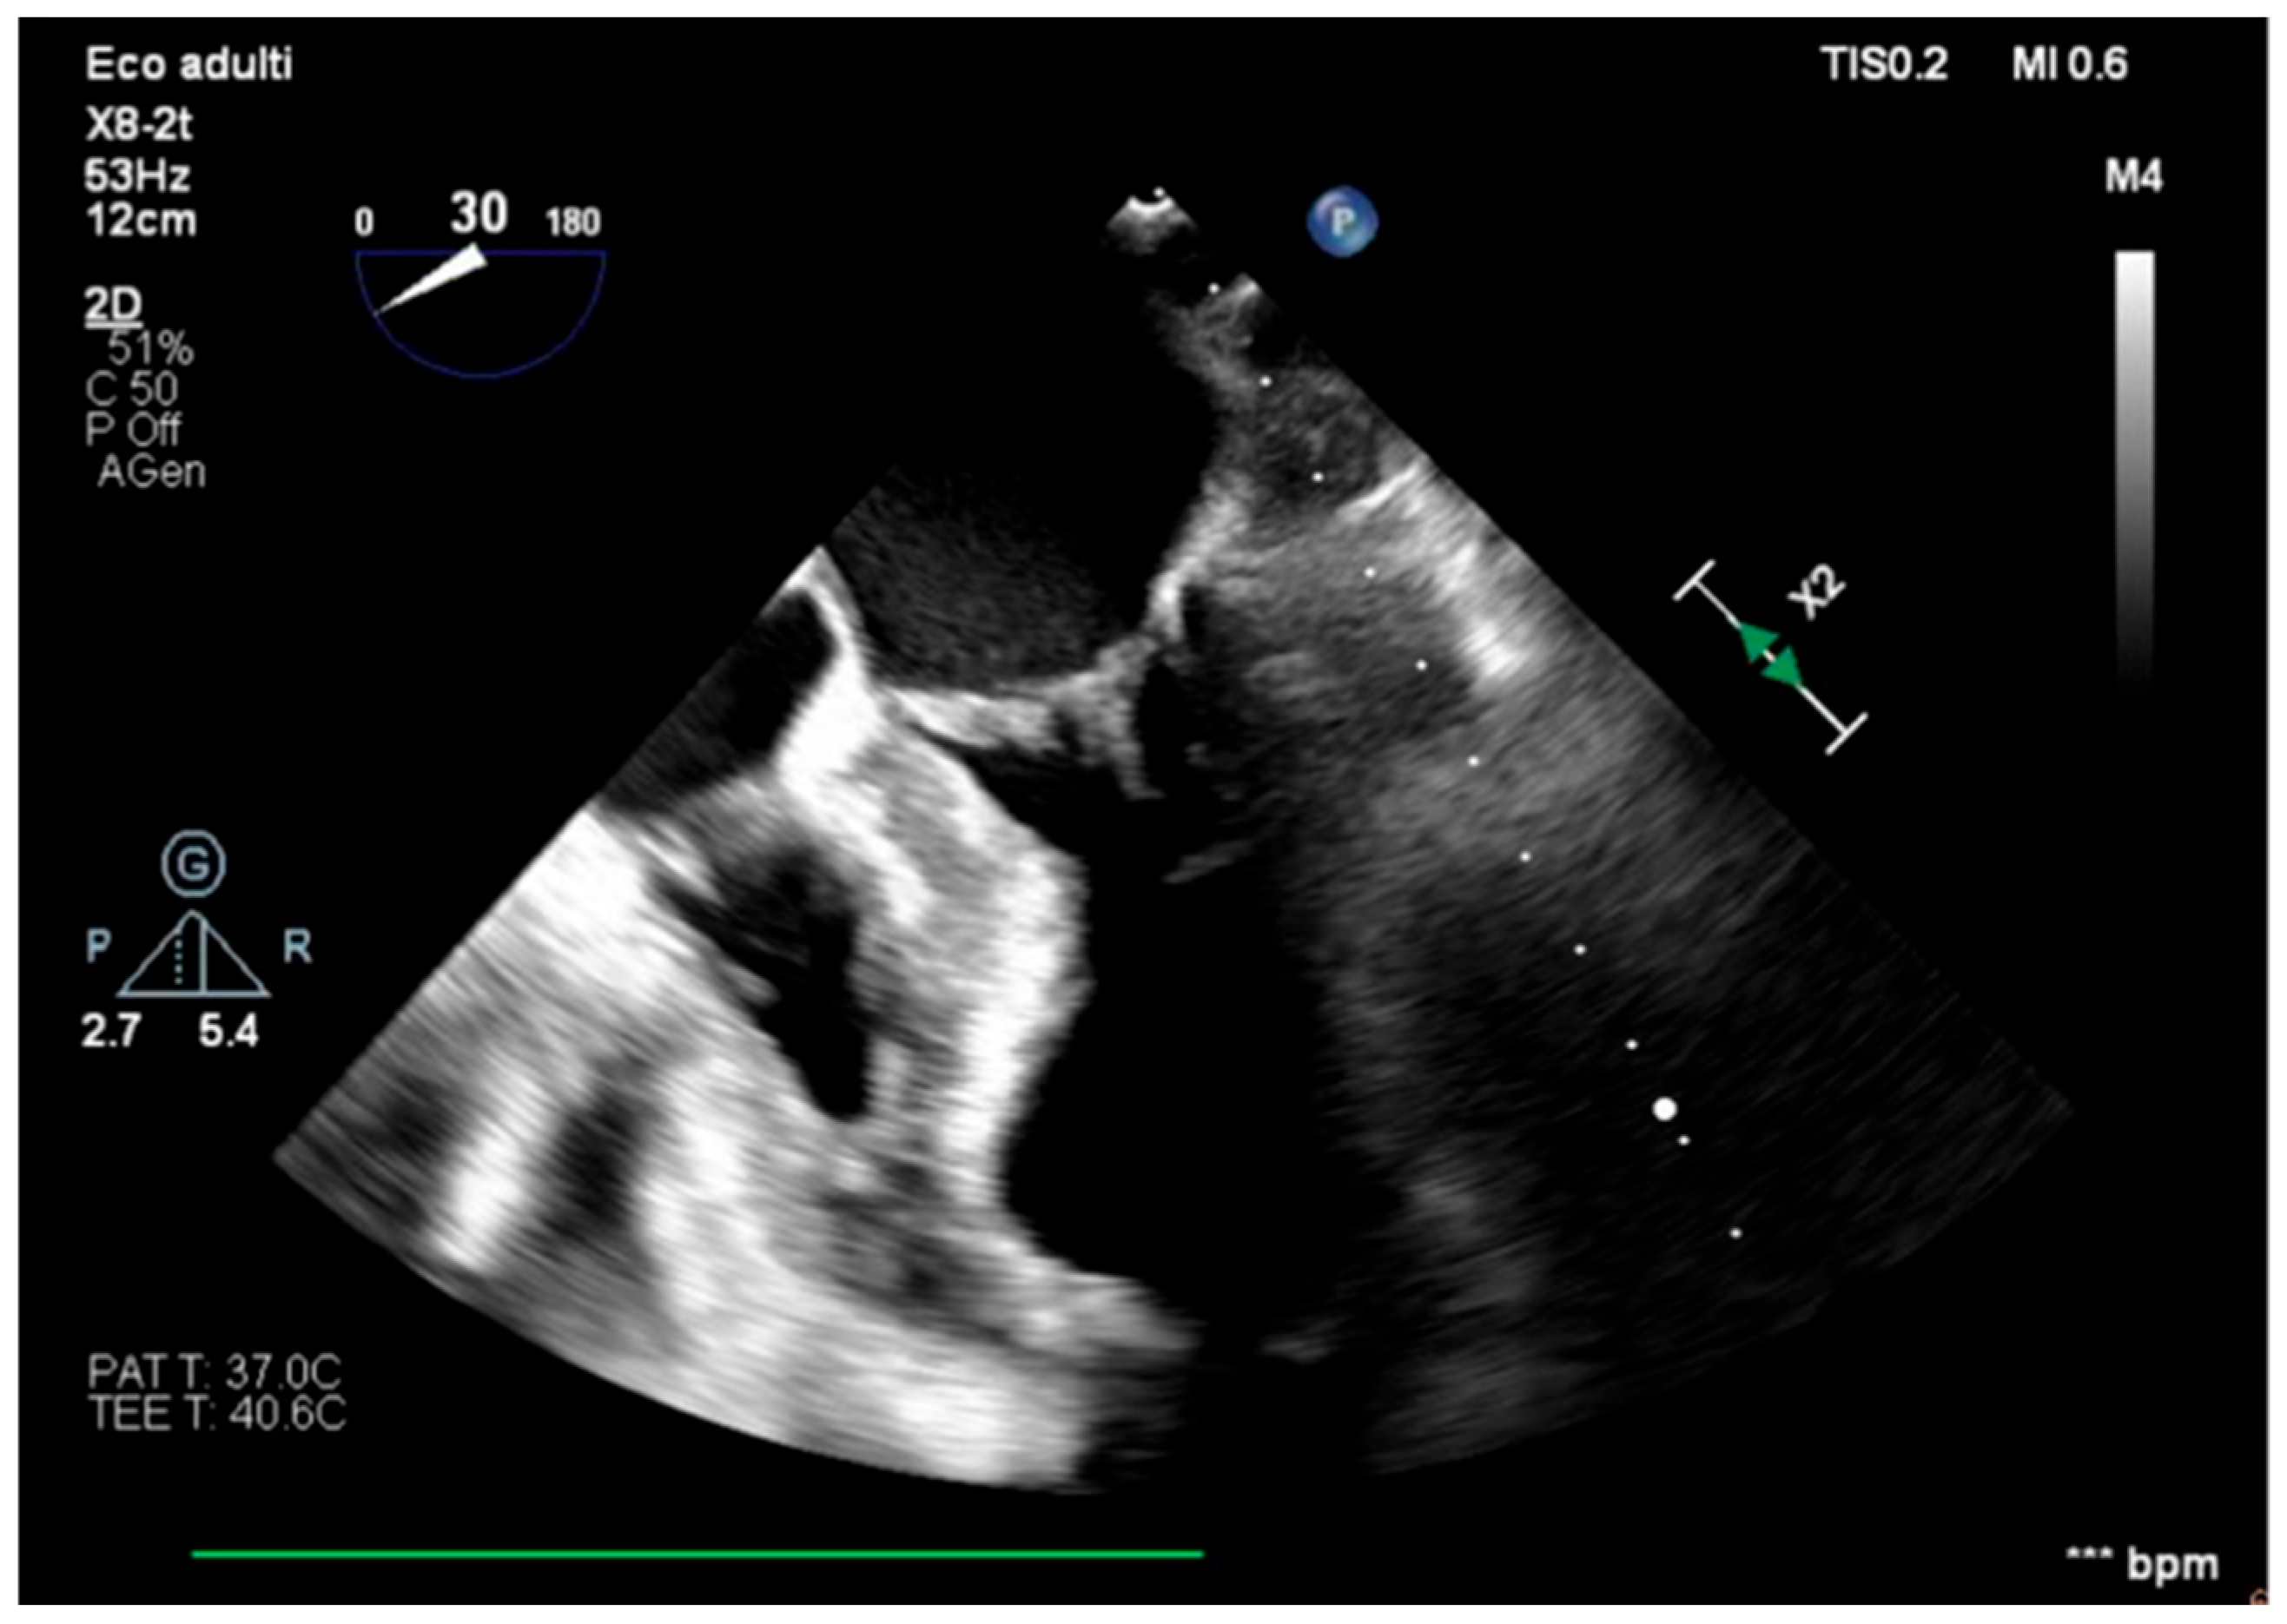

We describe a case of a 75-year-old woman affected by a post-myocardial-infarction ventricular septal defect (VSD) and a left-ventricle (LV) apical aneurysm. The patient underwent surgery for VSD closure and aneurysm exclusion. The patient had a STEMI (ST-elevation myocardial infarction), with evidence of occlusion of the anterior interventricular artery, for which thrombus aspiration and stenting of the left coronary artery and proximal anterior interventricular artery was performed. Then, she developed cardiogenic shock with pulmonary edema and thus required the support of an IABP (intra-aortic balloon pump) of C-PAP and levosimendan in continuous infusion for 24 h. Seven days after the event, a large post-infarct VSD at the apical level with a left–right shunt occurred. She was therefore transported from the spoke center to our hospital and underwent surgical treatment, namely, post-infarct VSD closure and exclusion of a left ventricular aneurysm. The intra-operative transesophageal echocardiography showed concentric LV remodeling, slight dilatation, LVEF 28% (Figure 1), and akinesia of the mid-apical segments in toto with aneurysmal evolution (Figure 2).

Figure 2. Trans-gastric view, apical level (short axis).